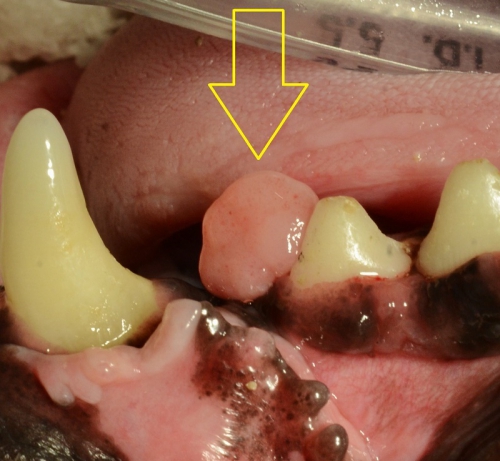

まず、エプリスとは何かという説明として下の2枚の写真をご覧ください。写真は上顎の犬歯のすぐ後ろから発生した良性の骨性エプリス(骨形成性エプリス)ですが、前後の隣接する歯まで覆い隠すほどの大きさです。(右が拡大です)